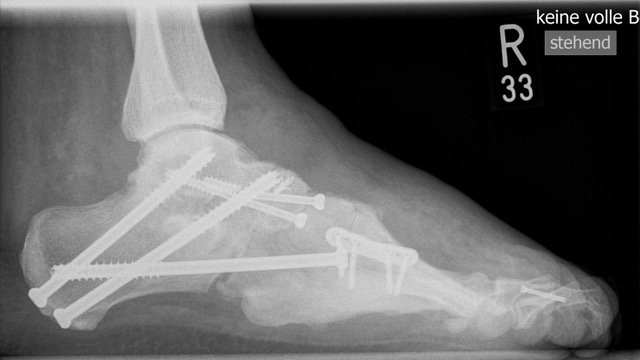

• Fuß belastet dp und seitlich (Abb. 14 und 15)

Typische Merkmale der Standard-Seitaufnahme des Fußes im Stand

• Knöchelgabel ist außen rotiert

• Talus und Calcaneus verlaufen fast parallel

• Sinus tarsi ist einsehbar

• Subtalare Gelenklinie verläuft horizontal und ist breit einsehbar

• Der Abstand Malleolus medialis zum Os naviculare ist verkürzt

• Der Calcaneus erscheint verkürzt

• Der Krümmungsscheitel des Fußes ist erhöht

• Calcaneus pitch ist meist erhöht, der Rückfuß Equinus ist eher selten 12